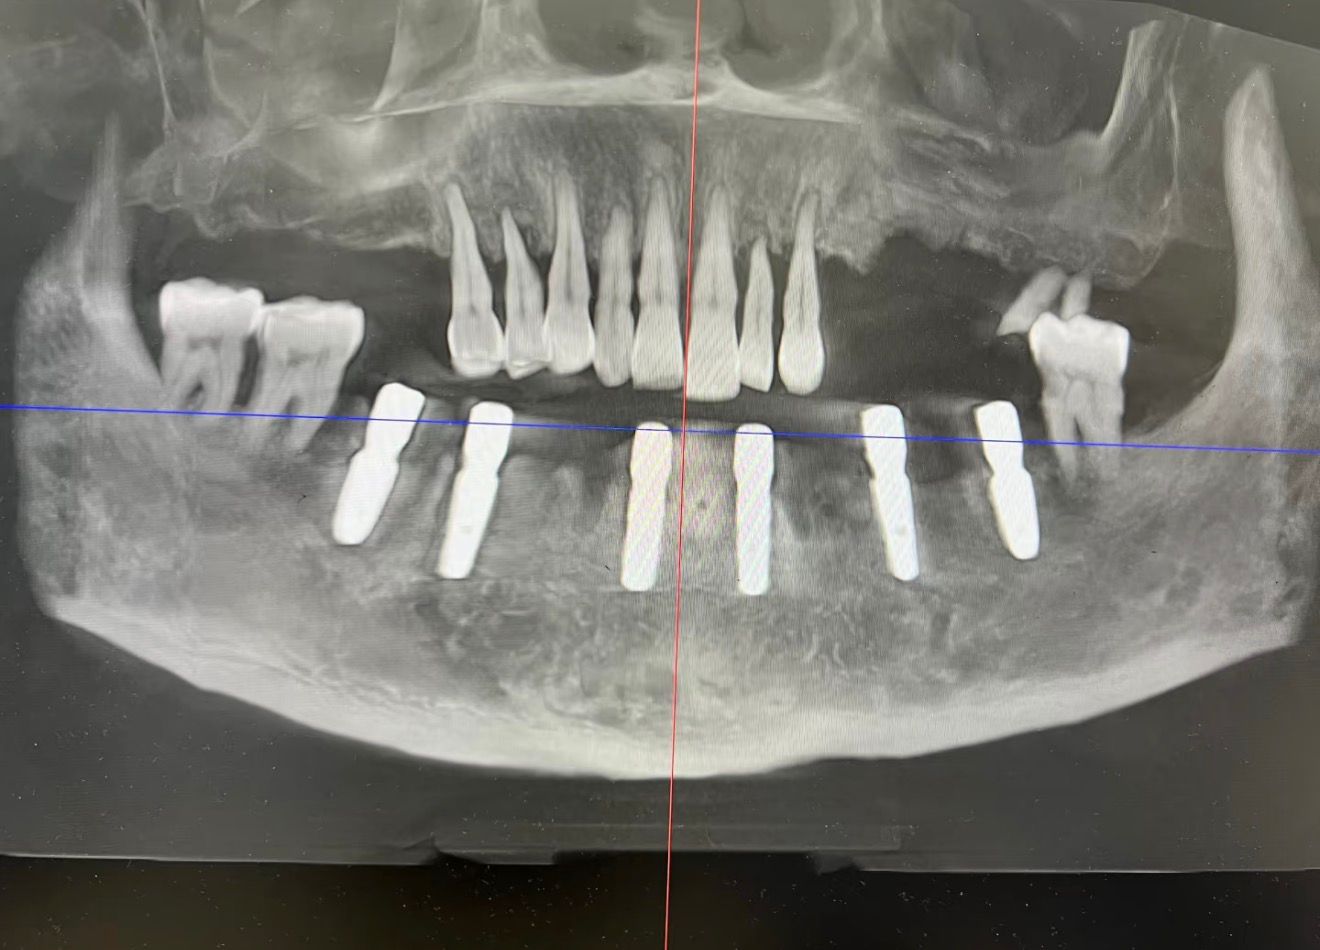

Примеры имплантации зубов в Хуньчуне